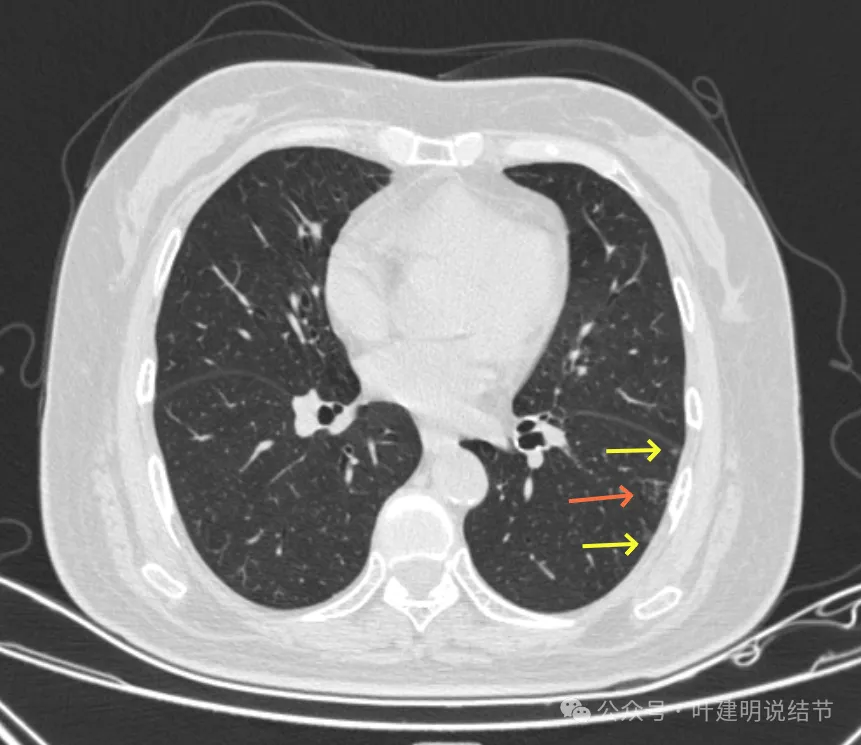

病灶1-4:两肺多处淡磨玻璃结节,密度低,散在,轮廓较清。

病灶41-43:左下叶多发结节,密度淡,桔色的病灶似乎有小空泡征的样子,但密度很低。